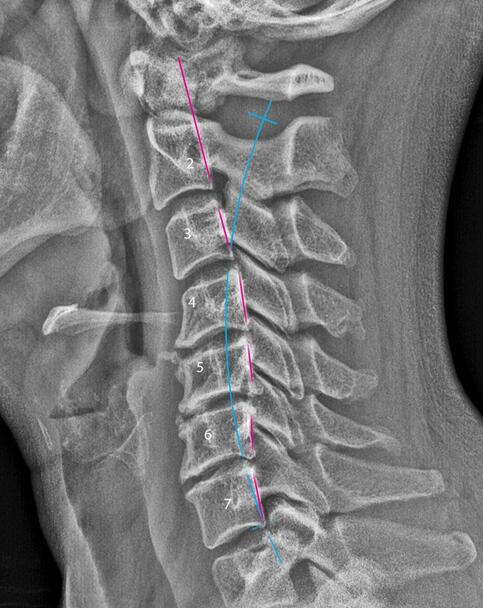

Imaging, when appropriate – to better visualize joint integrity, degeneration, or structural change

WHEN IMAGING IS HELPFUL

Not every case requires imaging, but in some situations it adds important context. Imaging can help:

Visualize joint degeneration or structural change

Clarify alignment patterns

Guide expectations and prognosis

Support informed care decisions

When recommended, imaging is used as a tool – not a shortcut – and always interpreted alongside clinical findings.